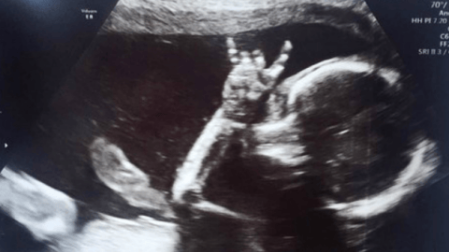

¡Que viva el rock! Bebé sorprende a padres en ecografía

Dos padres amantes de la música transmitieron sus gustos musicales a su hija, quien en un ultrasonido mostró una señal de rock

En esta ocasión, dos papás británicos sabían que su hija compartiría el amor por la música al igual que ellos. E so lo dejó ver una ecografía que se hizo Jodie Lee, la mamá de 31 años.

Jodie, junto a su pareja Davie Langham, de 32, acudieron a un médico en la zona este de Sussex, Inglaterra. Cuando vieron a su bebé, de 24 semanas, hacer la señal rockera quedaron sorprendidos y emocionados.

A pesar de que la fotografía no es reciente, pues Isla ya tiene 18 meses, apenas la compartieron y por eso se viralizó.

Algo nos queda claro: Isla ya rockeaba desde antes de nacer.